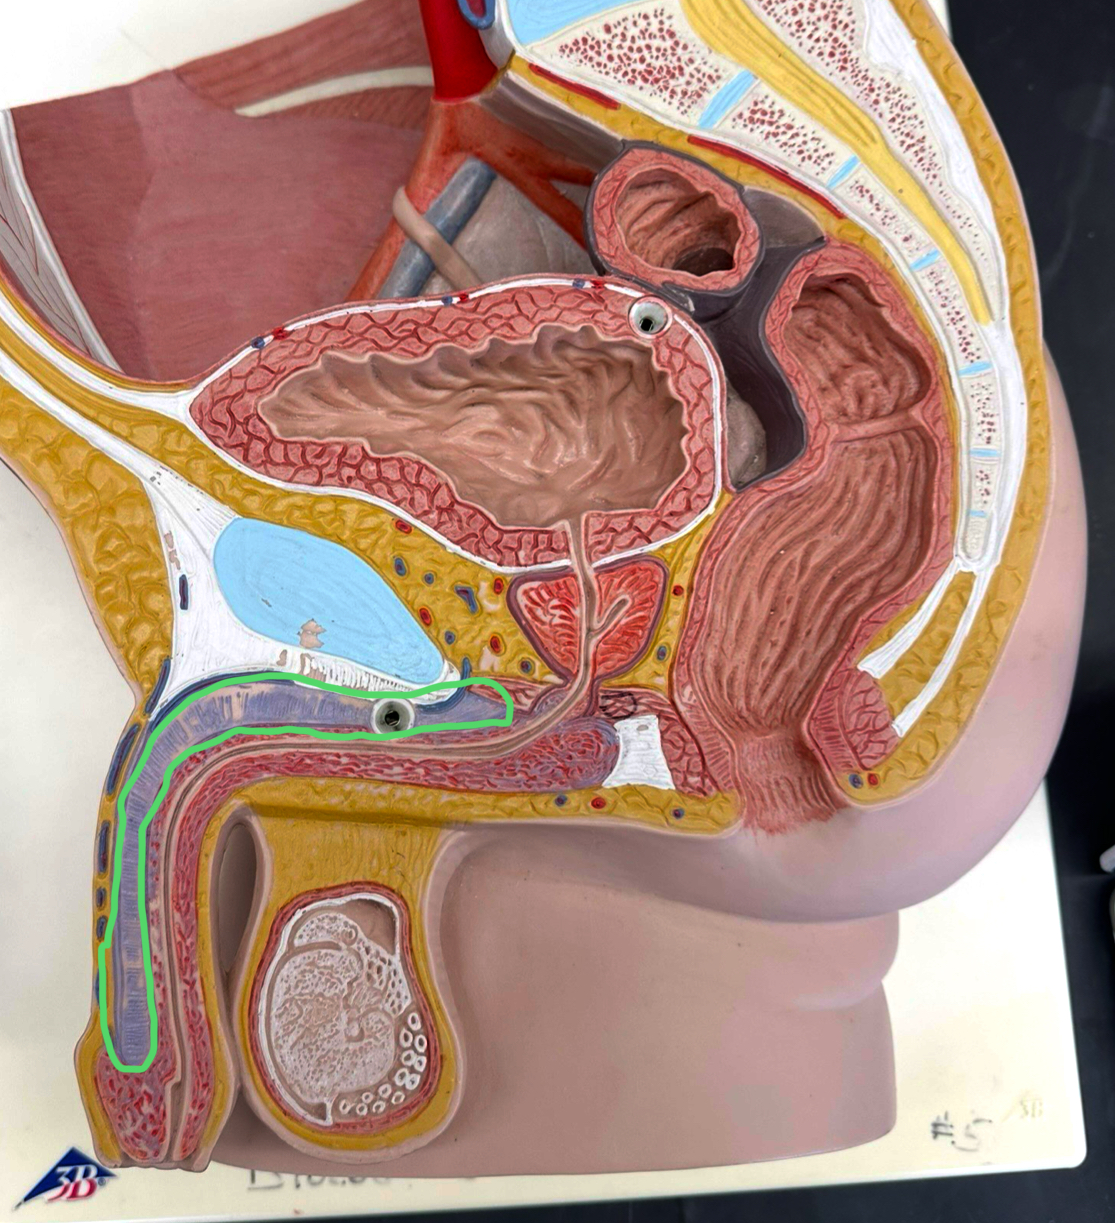

ductus deferens

ampulla of ductus deferens

ejaculatory duct

prostatic urethra

membranous urethra